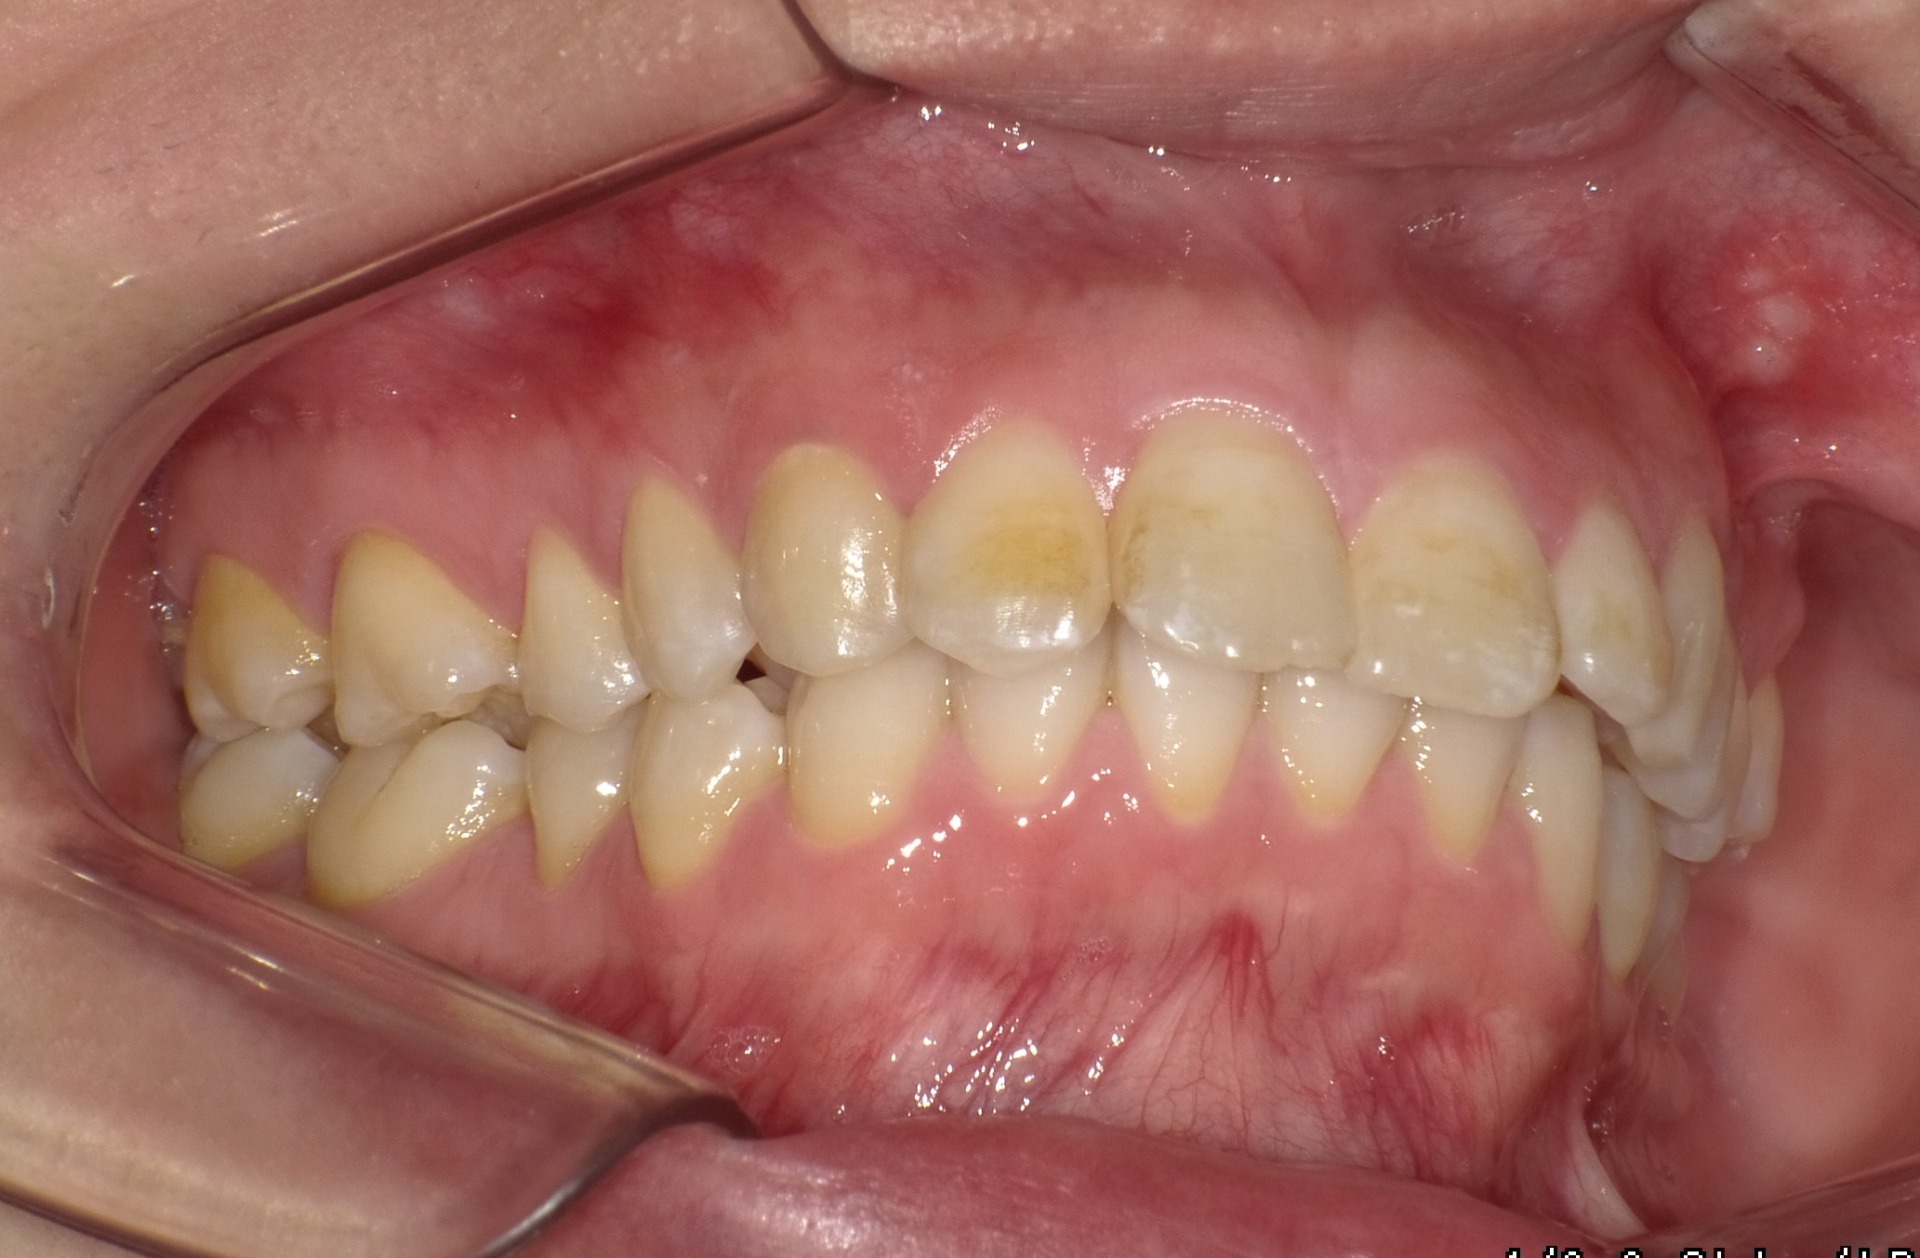

Before

| 症状 | 前歯が出ている |

| 通院目的 | 永久歯を抜かずに歯並びを治したい。 |

| 処置内容 | ディスタライザー・マルチブラケット装置 |